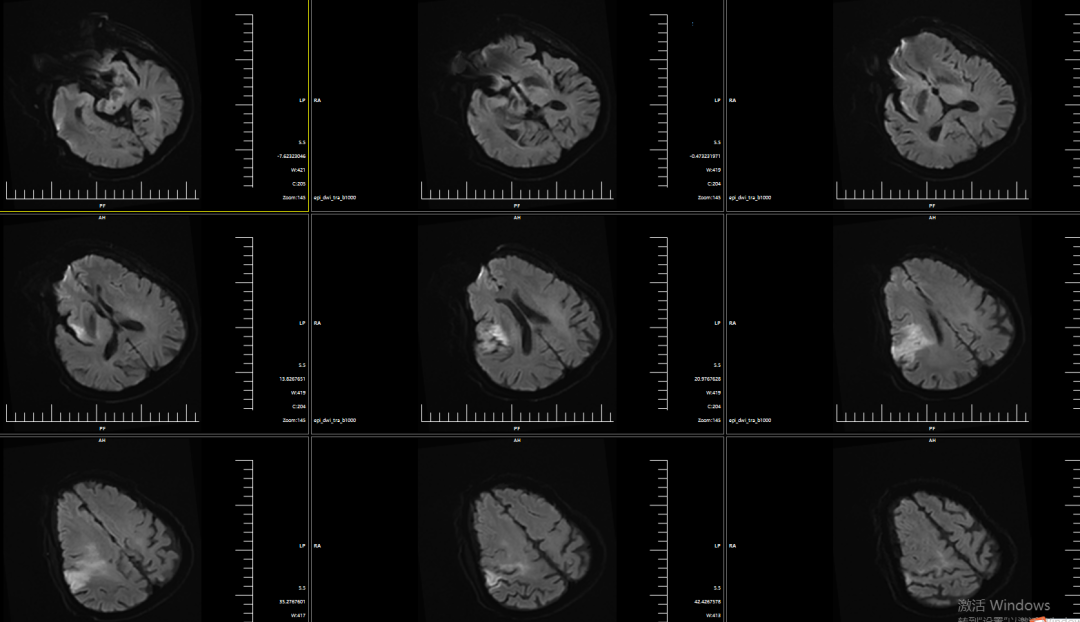

DWI提示右侧岛叶、右侧额顶叶明显弥散受限。

动脉长鞘怎么置入有励可说|Locaste 088励楷长鞘及Tarvos微导丝在右侧大脑中动脉M2段取栓术中的应用_https://www.jmylbn.com_新闻资讯_第5张

CTP提示核心梗死体积2.4ml,Mismatch体积160.8ml,低灌注区体积163.2ml,Mismatch比值为68。

动脉长鞘怎么置入有励可说|Locaste 088励楷长鞘及Tarvos微导丝在右侧大脑中动脉M2段取栓术中的应用_https://www.jmylbn.com_新闻资讯_第9张